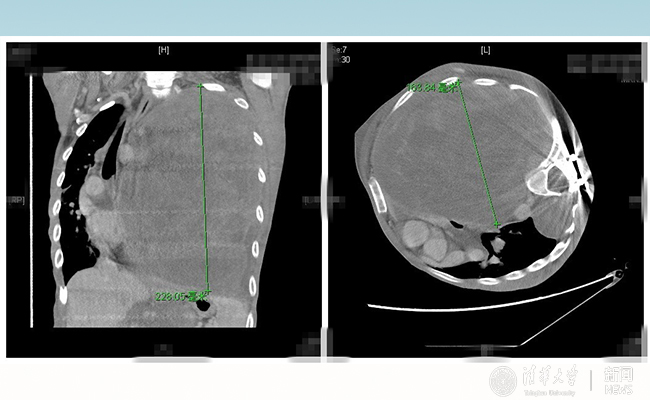

小飞的胸部CT提示:肿瘤在胸腔内已达22.8*16.3厘米。“相当于在胸腔里占据了1.5个肺脏的位置。”胸外科陈东红医师说。接收一个重症的患者,救命和保命将是一项系统的工程。由副院长王劲主持,胸外科、神经外科、麻醉科、重症监护室、输血科、影像科联合病例讨论,诊断患者为神经纤维瘤病Ⅰ型(以下简称“NFⅠ”),同时达成共识,虽手术风险极高,但却是唯一的希望。NFⅠ是一种常染色体显性遗传的家族性疾病,由肿瘤抑制基因突变而致。2006年,据约翰霍普金斯大学研究者报道,NFⅠ发病率为1:2 500~1:3 300。

患者术前肿瘤CT影像。